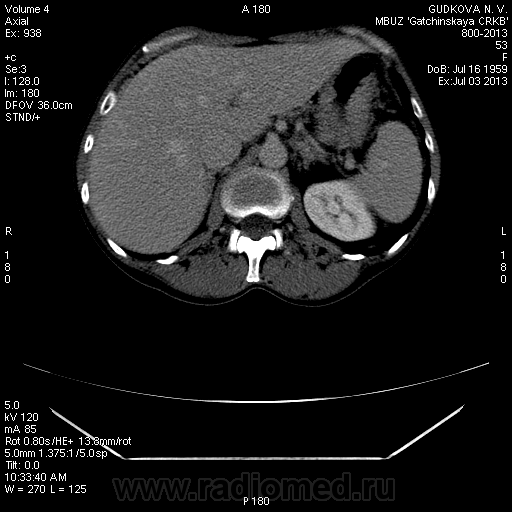

В артериальную фазу - интенсивное накопление контраста, как раз в области этого расширения, в 4-5 сегментах печени.Выше и ниже - идет неизмененная НПВ, без контраста (фаза артериальная!) В венозную фазу - небольшая гиперденсная зона перикавально в печени - и все.

На 3d-реконструкциях выглядит как кавернозная гемангиома, по форме напоминающая желчный пузырь (который я, кстати, не вижу, а УЗИсты описывают) Если это - ж.п., почему так интенсивно копит контраст, и вообще, расположение такое нетипичное?

Образование печени ли это вообще? Не перикавальное внепеченочное нечто? (и что?)

Это нижняя полая. Заброс контраста в нижнюю полую вену и контрастирование веточек портальной вены в артериальную фазу бывает при неправильной технике проведения болюса. Посмотрите тут: http://www.radiographia.ru/sites/default/files/abdominal_ct_protocols.pdf

Заброс контраста в нижнюю полую в артериальную фазу может быть при пассивном венозном застое, как следствие перикардита или сердечной недостаточности.у меня один раз тоже такое было, голову сломала, но в Прокопе все же нашла.

Может быть это просто нормальное контрастирование нижней полой вены за счет почечных вен, а не заброс контрастного вещества?

Да, это нижняя полая вена.